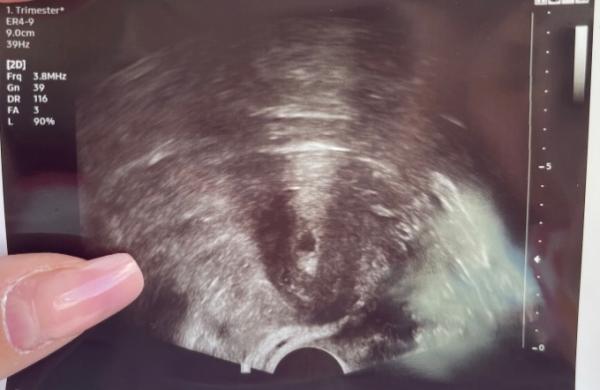

Hallo Mädels, ich war am Dienstag und Freitag beim Frauenarzt. Er konnte mir die Schwangerschaft bestätigen. Blut und Urin Werte sollen auch gut sein. Allerdings mache ich mir bisschen sorgen auch wenn der Arzt sagt alles sieht gut aus. Ich Google rum nach Ultraschallbildern die genau so in der Woche sind wie ich. Bei den Ultraschallbildern sind mehr zu sehen als bei mir. Wie war es bei euch?

Bild zu 6+1 7 ssw - Schwanger - wer noch? Rund um die Schwangerschaft

Dieses Bild ist vom Dienstag da soll ich 5+5 sein Das Bild oben vom Freitag